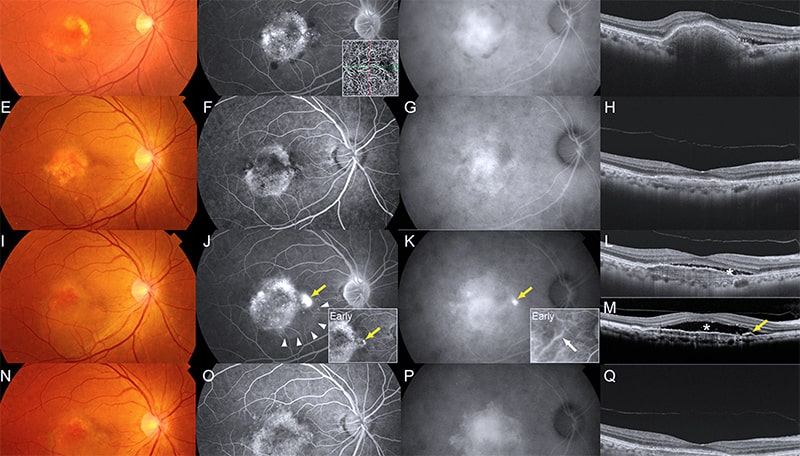

Для точной диагностики центральной серозной хориоретинопатии используются различные методы обследования. Визометрия позволяет определить остроту зрительных функций и оценить степень запущенности патологического процесса. Офтальмоскопия на фоне расширенного зрачка проводится с помощью асферической линзы или линзы Гольдмана, что позволяет увеличить изображение глазного дна и выявить дефекты пигментного эпителия, отслойку нейроэпителия и наличие прозрачной жидкости под сетчаткой, которая со временем может стать мутной.

Оптическая когерентная томография оценивает толщину и состояние структур глаза, включая сетчатку и сосудистую оболочку, а также определяет наличие жидкости под сетчаткой и высоту отслойки эпителия. Этот метод является основным для постановки диагноза и оценки результатов лечения. Флюоресцентная ангиография позволяет оценить состояние сосудов и выявить феномен пропотевания жидкости через патологические дефекты сосудистой оболочки. На основании этого обследования составляется план лечения и прогнозируется его исход.